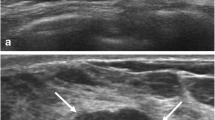

Shear wave elastography (SWE) is an emerging technique which can obtain quantitative elasticity values in breast disease. We therefore evaluated the diagnostic performance of SWE for the differentiation of breast masses compared with conventional ultrasound (US). Conventional US and SWE were performed by three experienced radiologists for 158 consecutive women who had been scheduled for US-guided core biopsy or surgical excision in 182 breast masses (89 malignancies and 93 benign; mean size, 1.76 cm). For each lesion, quantitative elasticity was measured in terms of the Young’s modulus (in kilopascals, kPa) with SWE, and BI-RADS final categories were assessed with conventional US. The mean elasticity values were significantly higher in malignant masses (153.3 kPa ± 58.1) than in benign masses (46.1 kPa ± 42.9), (P < 0.0001). The average mean elasticity values of invasive ductal (157.5 ± 57.07) or invasive lobular (169.5 ± 61.06) carcinomas were higher than those of ductal carcinoma in situ (117.8 kPa ± 54.72). The average mean value was 49.58 ± 43.51 for fibroadenoma, 35.3 ± 31.2 for fibrocystic changes, 69.5 ± 63.2 for intraductal papilloma, and 149.5 ± 132.4 for adenosis or stromal fibrosis. The optimal cut-off value, yielding the maximal sum of sensitivity and specificity, was 80.17 kPa, and the sensitivity and specificity of SWE were 88.8% (79 of 89) and 84.9% (79 of 93). The area under the ROC curve (Az value) was 0.898 for conventional US, 0.932 for SWE, and 0.982 for combined data. In conclusion, there were significant differences in the elasticity values of benign and malignant masses as well as invasive and intraductal cancers with SWE. Our results suggest that SWE has the potential to aid in the differentiation of benign and malignant breast lesions.